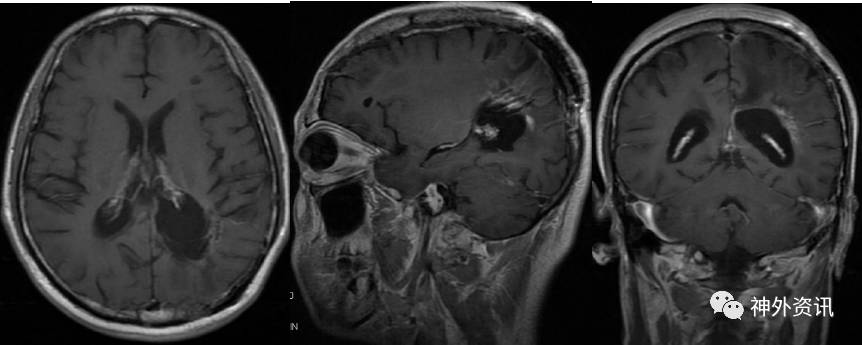

目前患者病情稳定,已经密切随访半年余,除右侧同向性偏盲外,无其他明显症状和体征,KPS评分90分。复查头颅MRI增强示(2017.02.13):左侧脑室后角旁不规则形异常信号,呈T1、T2等信号,内见条状T2低信号影,增强后呈部分强化,周围脑组织水肿,左侧脑室后角扩张。对比前片(2016-08-22)左侧脑室后角及三角部旁病灶相仿(图8)。

图8. MRI检查::左侧脑室后角旁不规则形异常信号,呈T1、T2等信号,内见条状T2低信号影,增强后呈部分强化